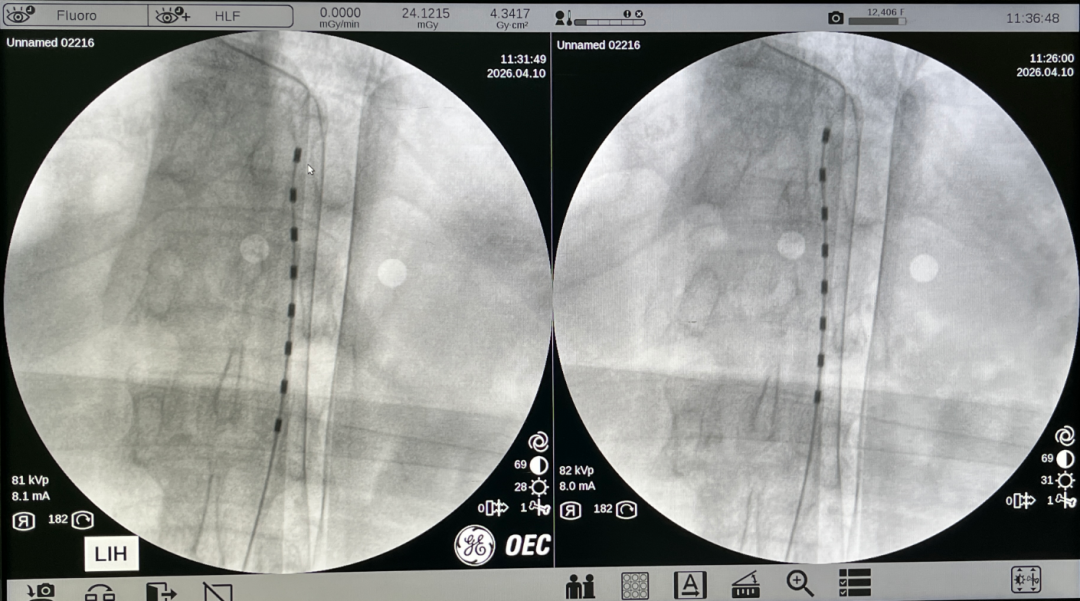

针对患者的复杂病情,张永祥团队精准评估后,制定了短时程脊髓电刺激的个性化手术方案。手术在局部麻醉下进行,借助影像设备实时引导,电极精准定位至T12-L1脊髓节段。测试刺激的瞬间,患者足部疼痛大幅缓解,双下肢出现清晰酥麻感,电极位置的精准度得到实时验证。